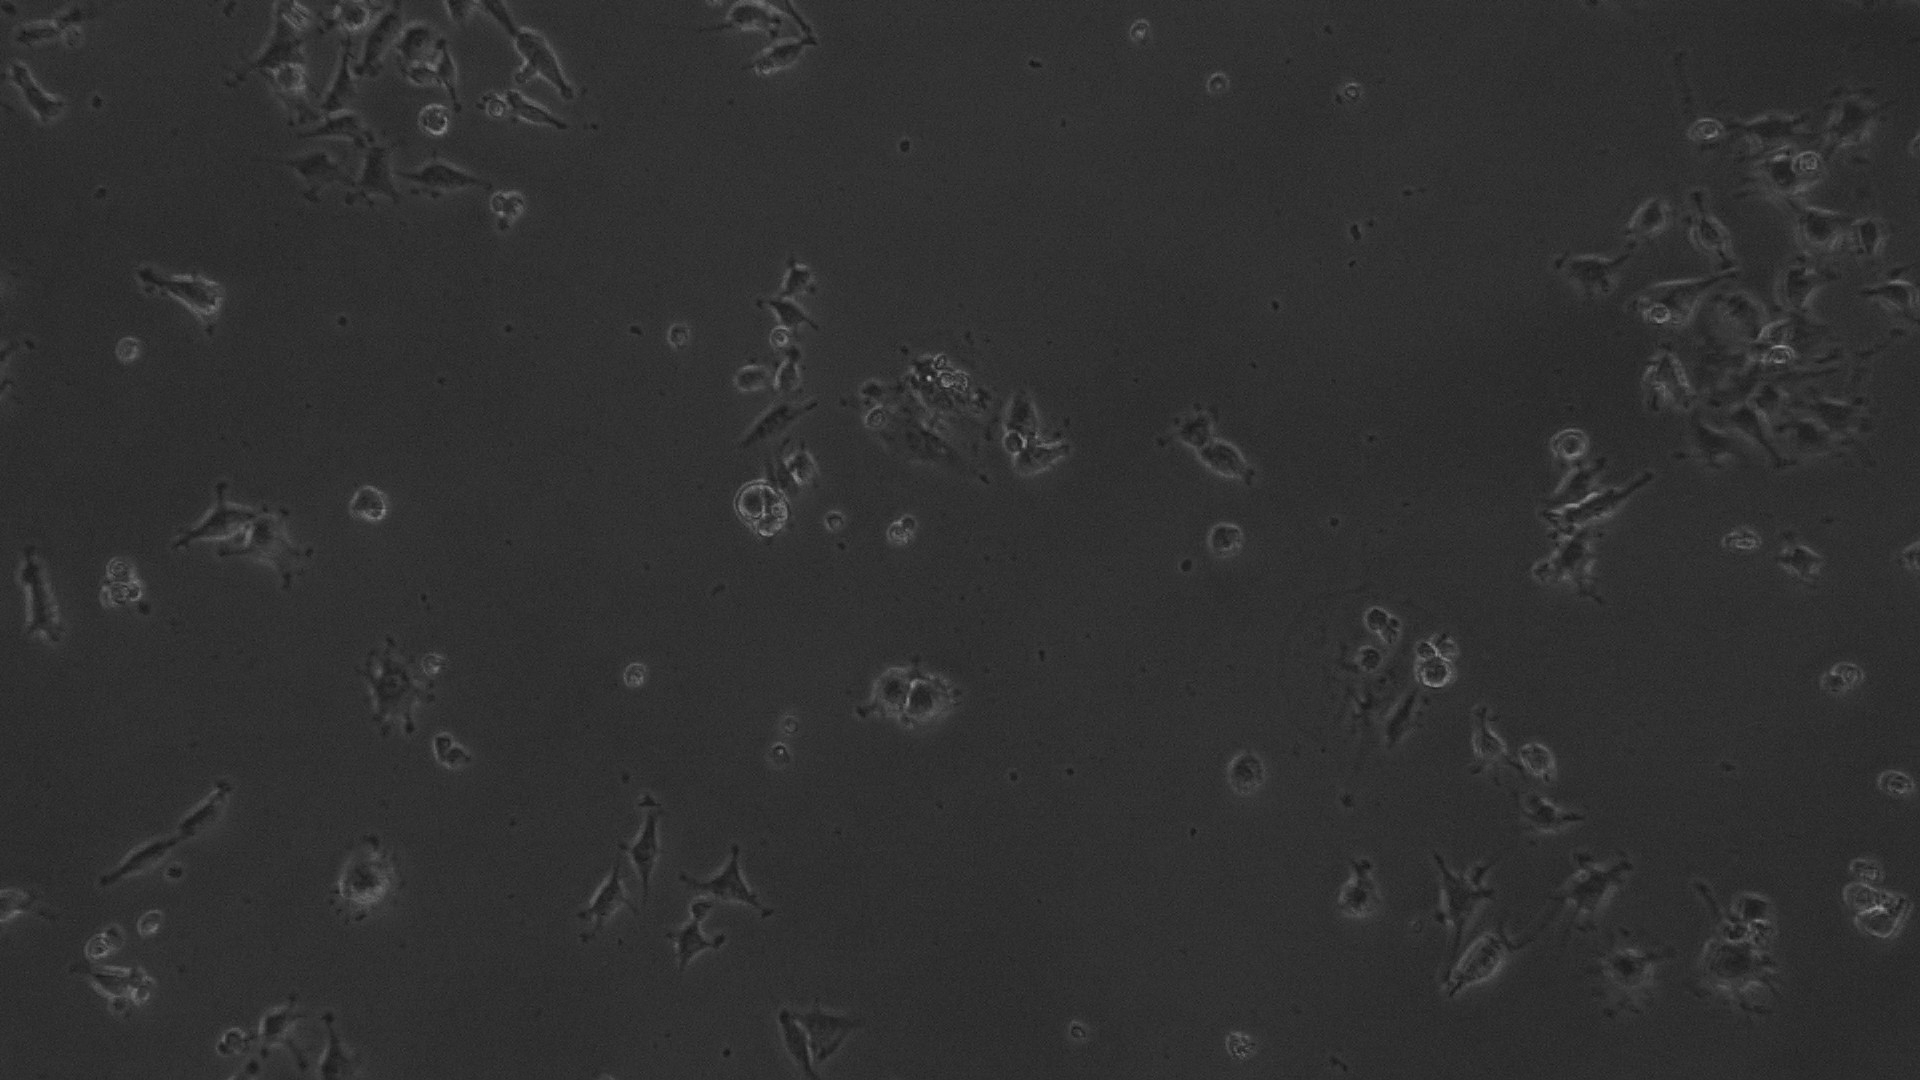

The entire plate was observed at an interval of every 24 h; up to 72 h in an inverted phase-contrast tissue culture microscope (Labomed TCM-400 with MICAPSTM HD camera) and microscopic observations were recorded as images. Any detectable change in the morphology of the cells, such as rounding or shrinking of cells, granulation, and vacuolization in the cytoplasm of the cells, were considered as indicators of cytotoxicity.

Fig. 7: Morphological changes showing inhibition of MCF 7 cell lines by different concentrations of ethanolic extract of leaves of Pothos scandens. a: -ve control (95% ethanol), b: 6.25 µg/ml, c: 12.5 µg/ml, d: 25 µg/ml, e: 50 µg/ml f: 100 µg/ml

In vitro anticancer actiivity of ethanolic extract of leaves of Pothos scandens Linn. was evaluated against HeLa and MCF 7 cell lines. The viability of cells was evaluated by direct observation of cells by an Inverted phase contrast microscope and MTT assay method. The morphological changes in HeLa and MCF 7 cells after treatment with the extract and standard doxorubicin are shown in fig. 5, 6, 7 and 8. The IC50 values are shown in table 4.